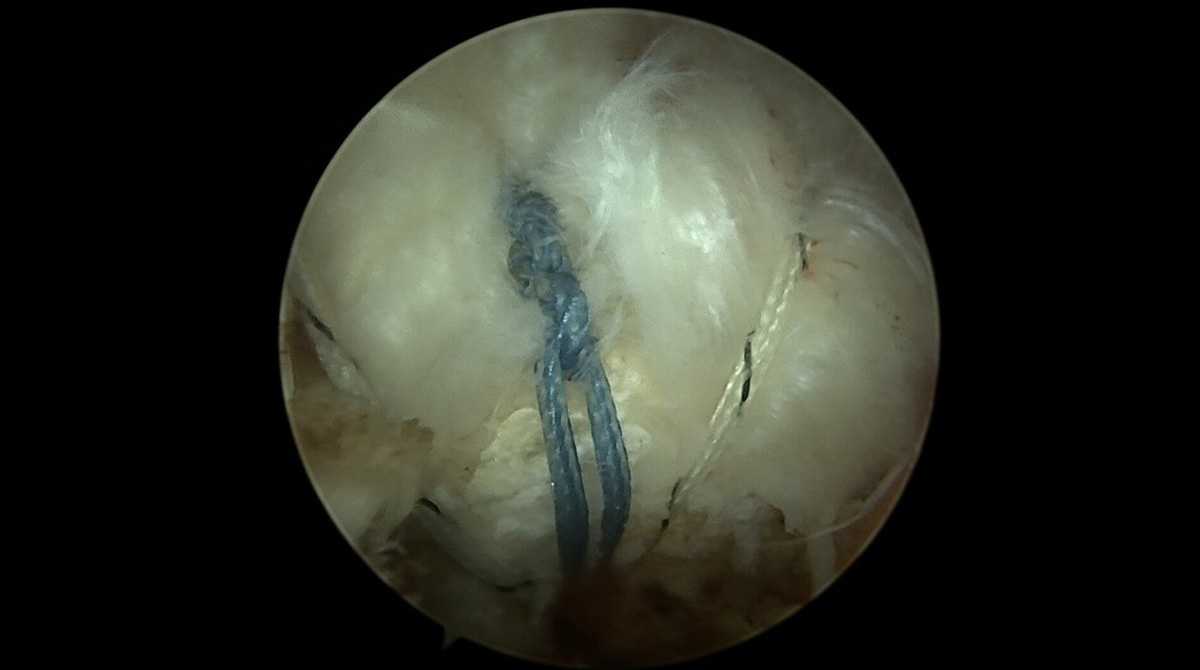

Cette intervention est actuellement réalisée sous arthroscopie, c’est-à-dire en rentrant une caméra et des instruments dans l’articulation de l’épaule par de petites incision centimétriques.

De multiples gestes peuvent être réalisés par cette technique. Les gestes réalisés dépendront du type et de la localisation de la rupture. Le but est de réinsérer les tendons abimés sur leur tubérosité. Cette réparation se réalise grâce à des systèmes de fils montés sur des ancres qui sont fixés dans l’os.